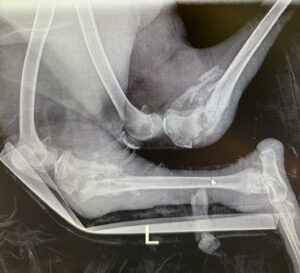

At the very beginning of July 2024, we admitted a coyote pup that had been hit by a car and was found lying on the side of a busy road. Vehicle accidents can be traumatic for wildlife, resulting in severe injuries and unforeseen complications. Once this pup had some time to rest, we were quick to complete an in-depth exam and preform X-rays. Upon exam, there were no broken bones, but he would not stand up or use h

is back legs and his stomach was swollen, a sign of possible internal damage from the accident. We consulted with our veterinarian, and agreed to just let the young coyote rest and recover. One of my favorite animals to work with, I was thrilled to have a chance to work with him, yet realistically worried he would not make it through the night. Yet, he did.

I estimated that this young pup was about three months old, probably born in April of 2024. He was weaned from his mother, but not old enough to leave his family unit yet. After allowing him a few weeks of rest, we planned to move him into an outdoor enclosure with enough space to run around and exercise, ensuring that all of his bumps and bruises had healed well, and then return him to the area where his pack lives. Filled with excitement, we moved him to the enclosure with expectations to release him the following day. Unfortunately, despite our efforts to limit dangerous obstacles in the pen, this wi

ld pup managed to trip and break both of his back legs overnight.

I was devastated – the very last thing a wildlife professional wants is for an animal to become injured in their care. Beyond this, I was not optimistic that this athletic, high-stress coyote would be able to recover from two broken legs. Once again, I consulted with our veterinarian and he assured me that we would be able to bandage the broken bones in-house and they should heal. So, we gave this pup our very best shot. Months of bandage changes, bedsores, medications, follow-up X-rays, and plenty of TLC resulted in something I truly was too afraid to hope for: a full recovery. To prevent a repeat of his injuries, we transitioned him very slowly into larger spaces as he healed.

For months of his recovery, the only way that I knew he was healing was through X-rays – he would rarely move for his daily cleaning and feeding indoors. While they can be fierce predators in the wild, this young coyote would cower away from his caretakers and only moved and ate at night when we were not around. This made his treatment safer and easier on our staff, but it did not provide any insight on how his legs were healing. Once he was healthy enough to transition to be housed in a small room in our clinic building, we installed a camera